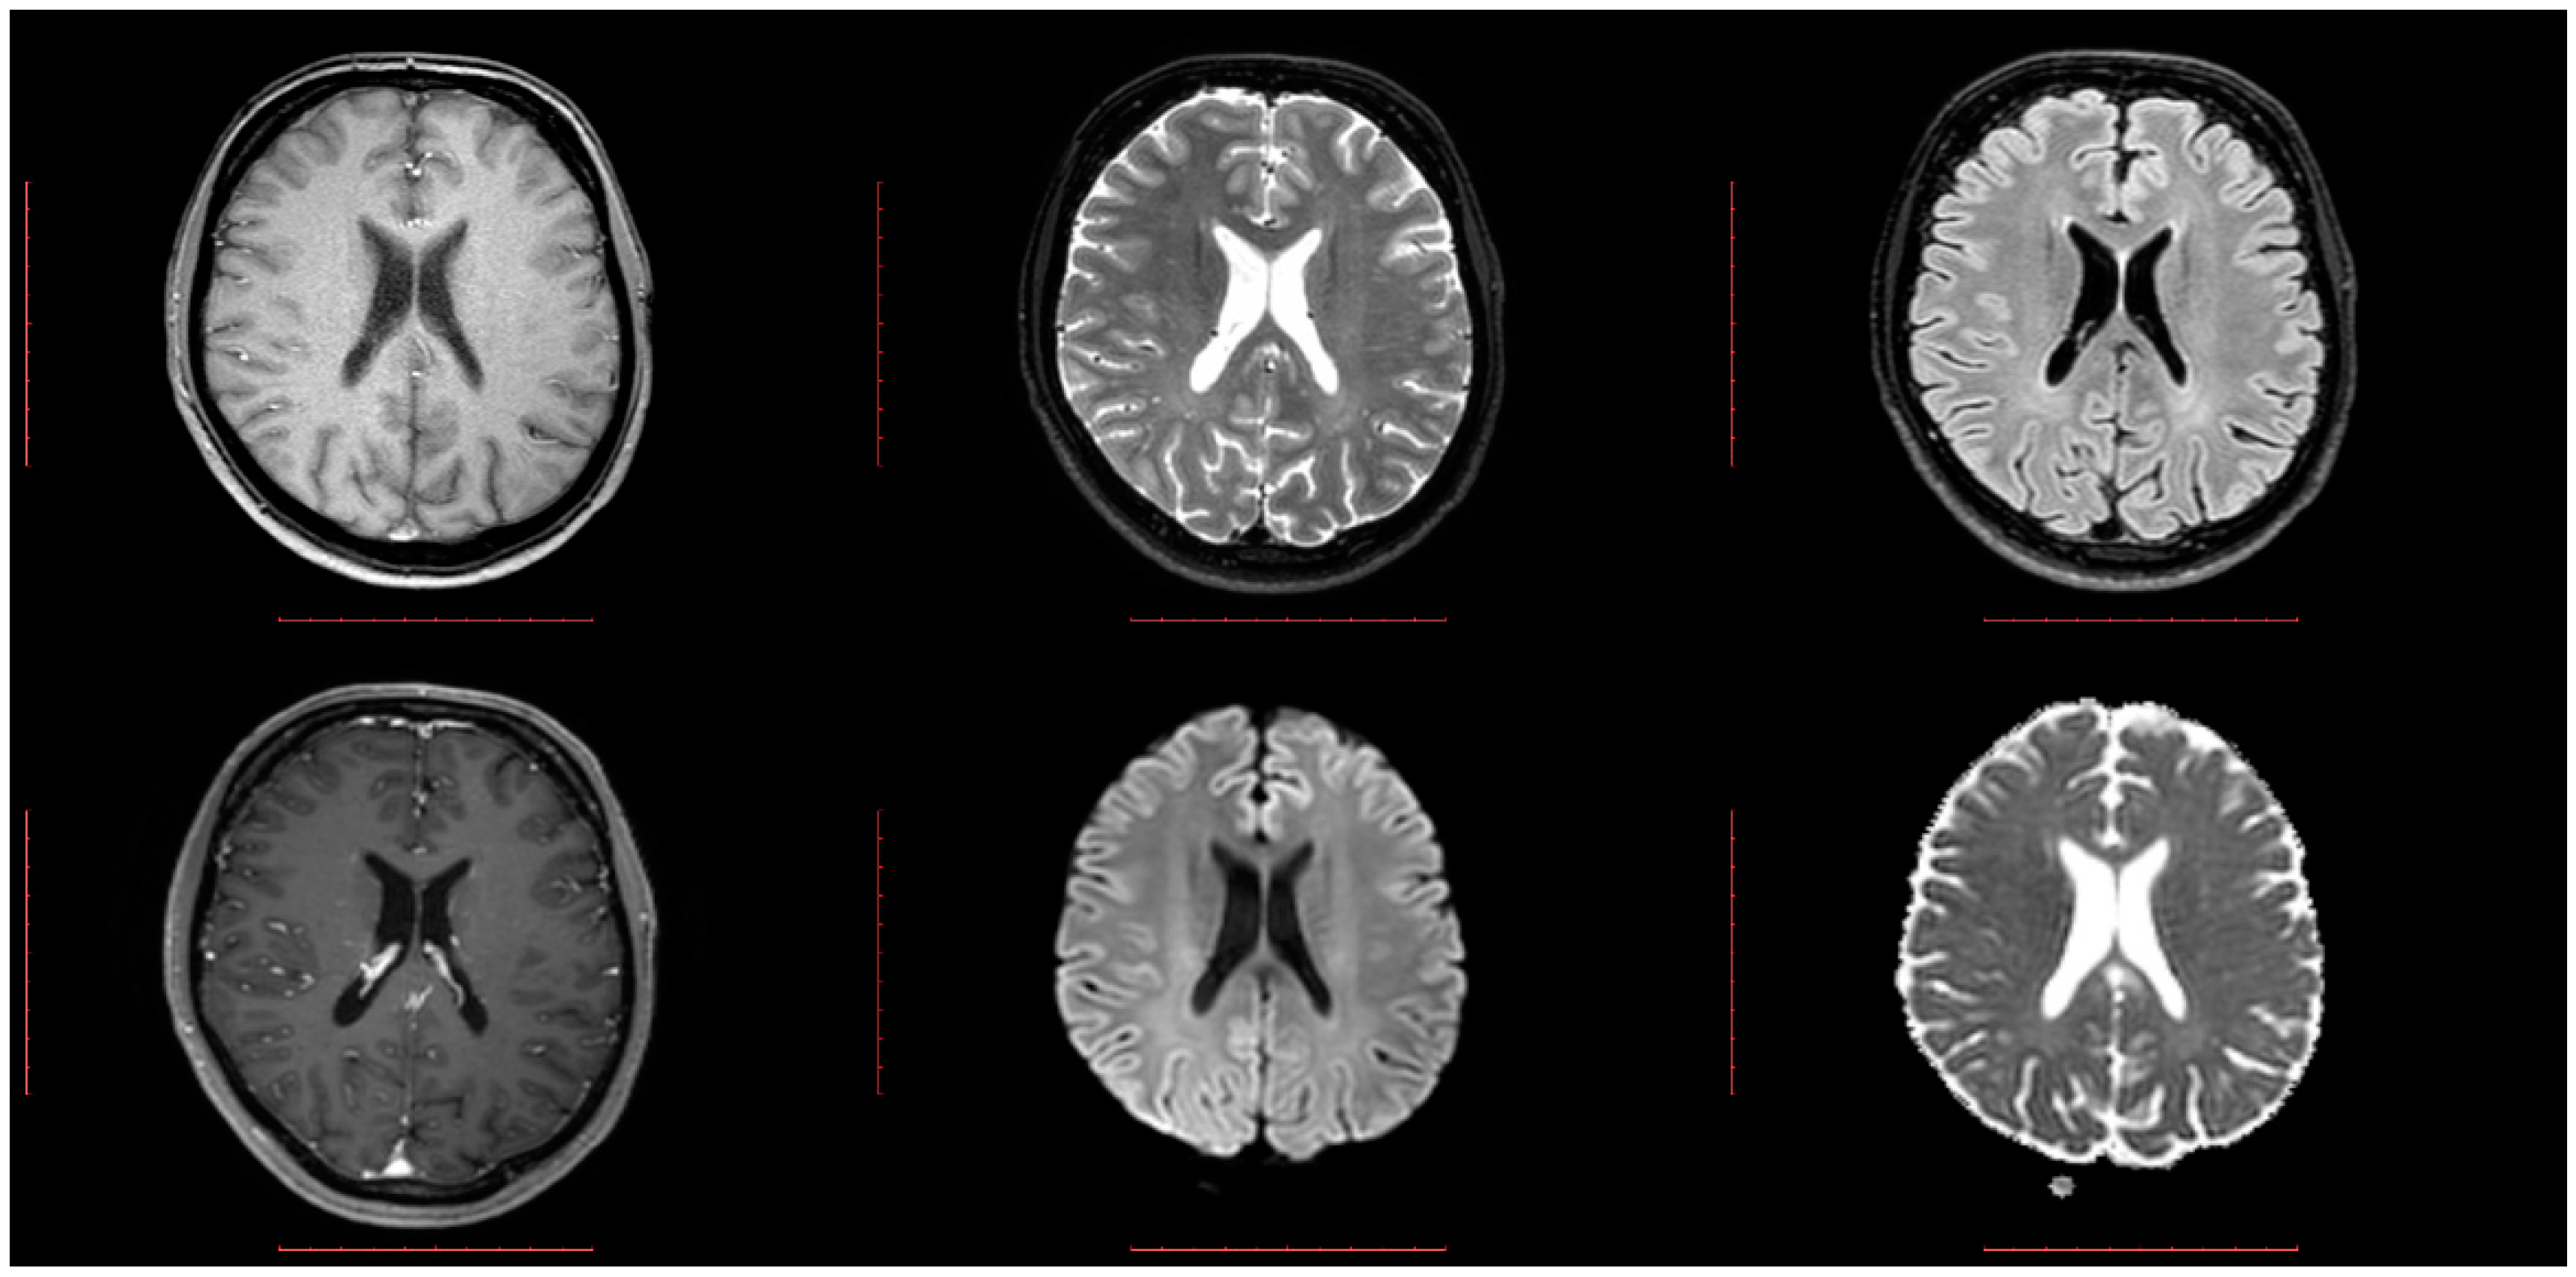

2.1. Dataset Collection and Preparation

2.2. Image Preprocessing